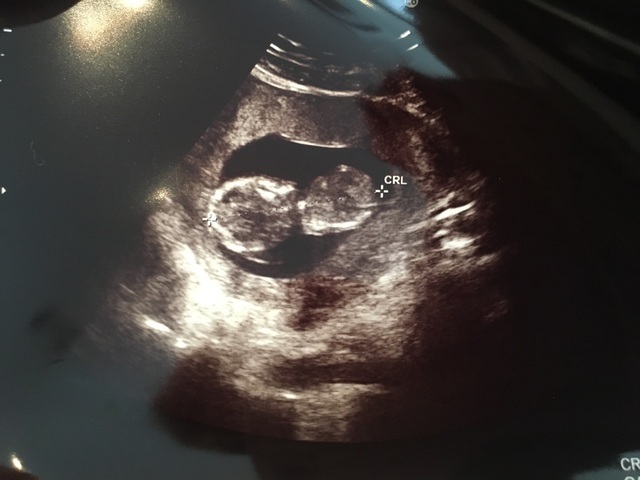

14週0日(14w0d・性別不明)|natsuki. さん(24歳)

エコー写真撮影時のエピソード:

3週間ぶりの検診で小心者の私のドキドキ、不安とは裏腹に前回の検診より成長しており一安心。初めて心音も聞かせてもらって、より一層実感が増しました。

内診中も凄い元気に飛び跳ねててかわいかったな。次の検診は4週間後なので今から楽しみ。